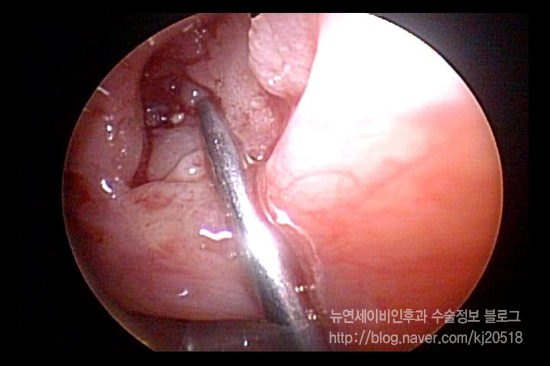

이렇게 계속 사용하면 이비인후과를 방문하여 제거할 필요가 전혀 없고, 그동안 불편하고 불쾌했던 부분을 생활 속에서 계속 사용해 해소할 수 있다는 것이 너무 신기했습니다. ^^